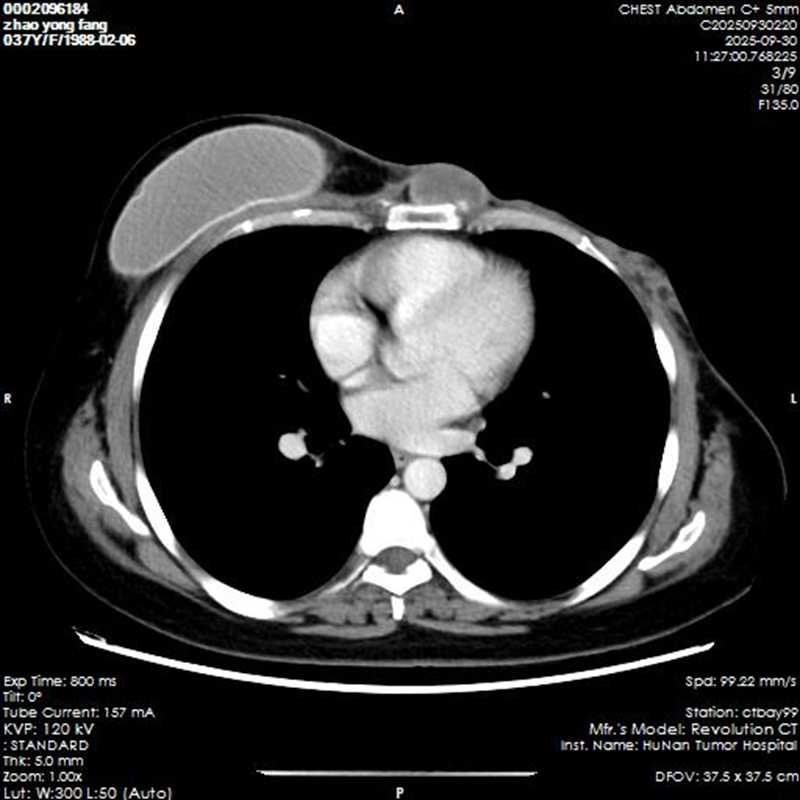

该患者此前因左乳恶性肿瘤已历经多次治疗,包括在省内多家三甲医院进行的三次手术及系统治疗,但病情仍未得到有效控制,此次确诊为胸壁梭形细胞肿瘤,且进展迅速,肿瘤已侵犯胸壁骨性结构。据省中医医护人员介绍,此时手术已成为控制病情、延缓肿瘤进展的关键手段,但其复杂性与风险度也让治疗面临巨大挑战。

10 月8日手术正式启动。此次手术需彻底切除胸壁复发肿瘤及受侵犯的肋骨、胸骨,术后胸壁缺损范围达28×25厘米,后续还需通过肋骨板重建胸壁骨架,并采用患者自体双侧腹部皮瓣及对侧乳房皮瓣完成创面覆盖与功能修复,整个过程步骤繁杂、风险极高,对团队技术水平与协作能力提出严苛要求。